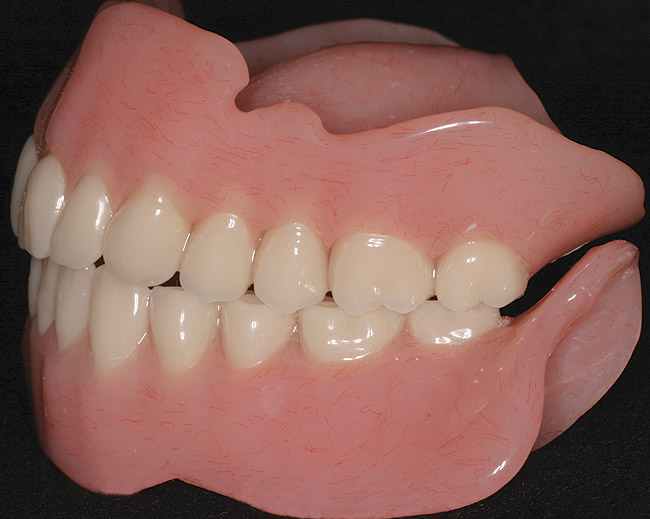

In overdenture therapy, prosthetic design can be divided into two groups: stress-broken and rigid. Stress-broken prostheses require fewer implants, with attention to biomechanical design features to allow for rotation (stress-breaking) of the prostheses around the implant locations. These prostheses are essentially tissue-supported and implant-retained. They replace the adhesive/glue, providing needed retention, comfort, and support. An example would include two implants in site Nos. 23 and 26, with either solitary anchor systems (ball or stud attachments) or a splinted bar-overdenture design (Figure 9 through Figure 11). Masticatory function is improved and patient satisfaction increased. Rigid prostheses require multiple implants, with the forces being transferred from the supra-infrastructure directly to the implants. These prostheses are implant-supported and implant-retained. The design can be removable or fixed (Figure 12 through Figure 16), depending on patient- and operator-mediated preferences.24-27 Within the fixed group of prostheses, materials used may vary from acrylic-fused-to-metal, porcelain-fused-to-metal, or all-ceramic. The cost of these material choices varies significantly, with acrylic options providing the most affordable, entry-level approach for the patient.14